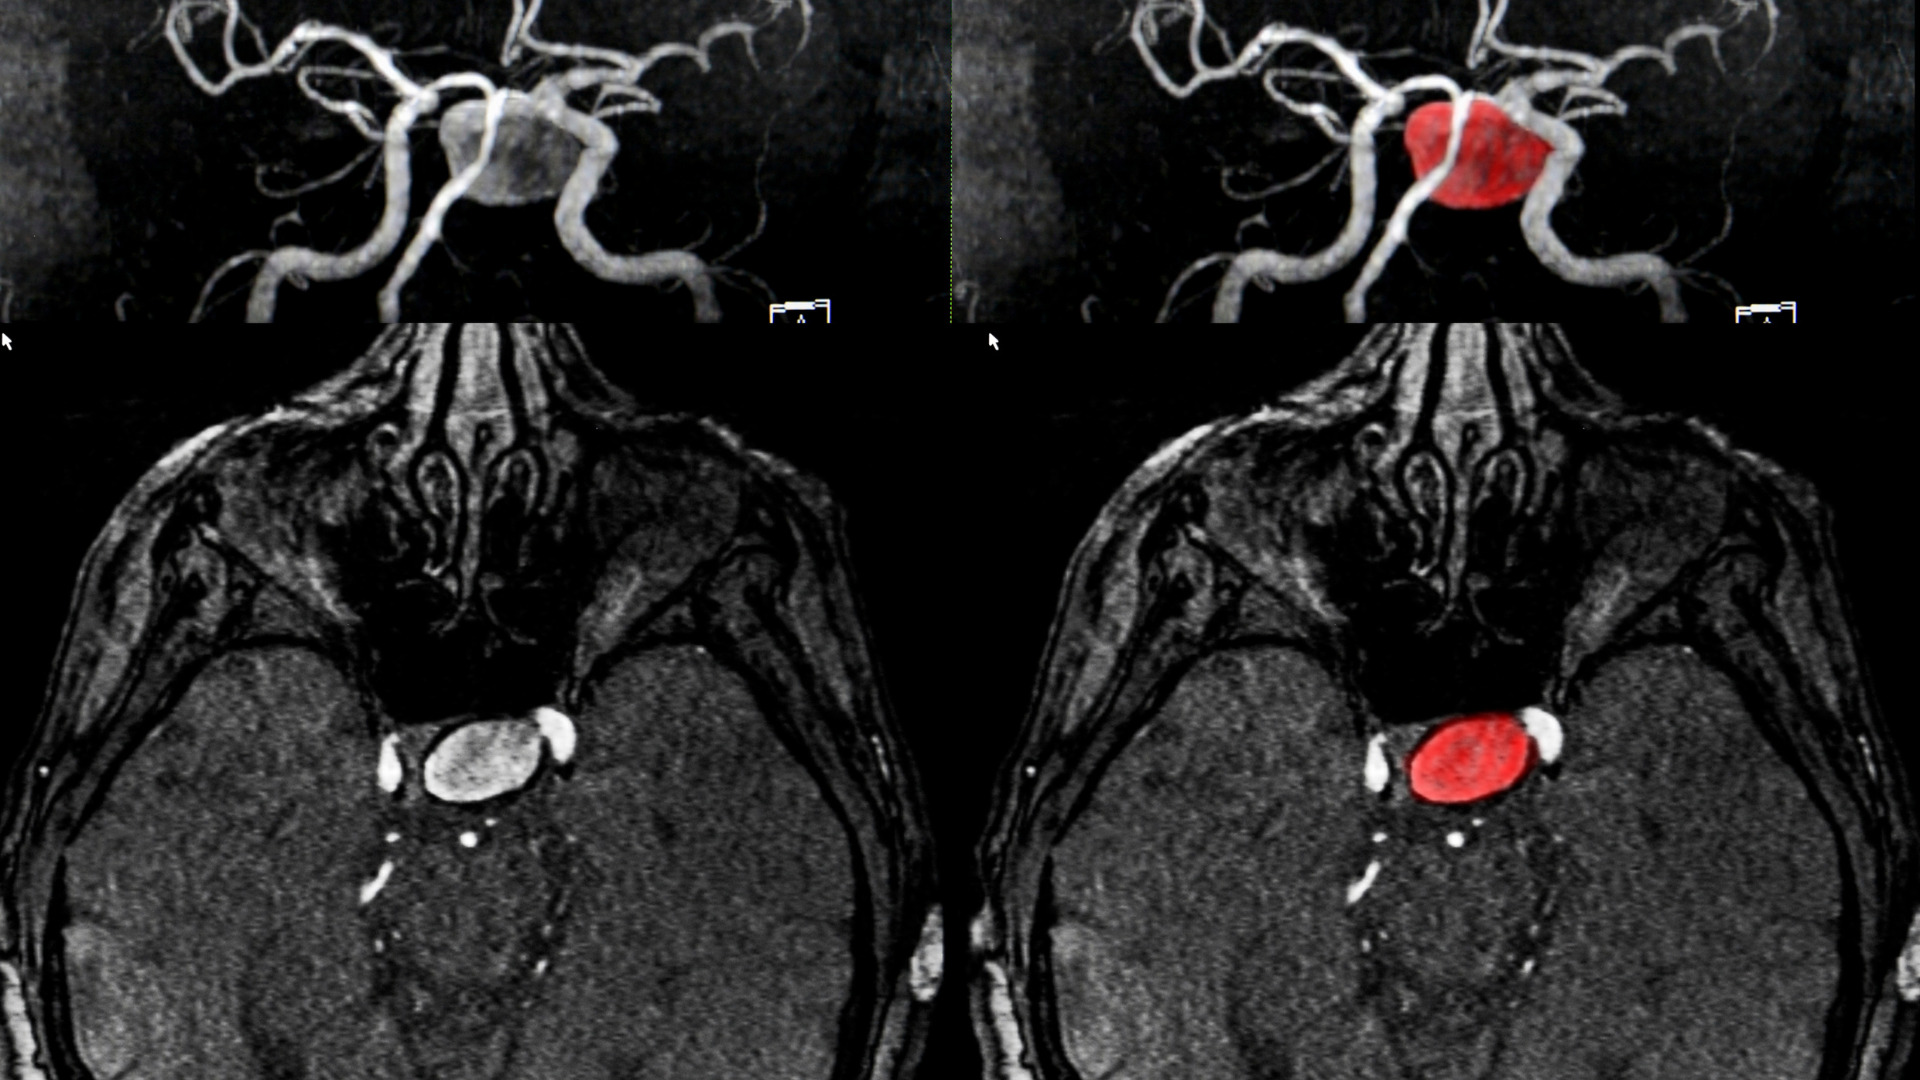

Ảnh minh họa.

Chụp CT (chụp cắt lớp vi tính): Chụp CT giúp bác sĩ xem xét tình trạng máu rỉ trong não bộ. Kỹ thuật này sử dụng tia bức xạ X để tạo ra hình ảnh một mặt cắt ngang hoặc tạo ra hình ảnh chi tiết về lưu lượng máu trong động mạch não. Kỹ thuật chẩn đoán hình ảnh này sẽ thể hiện kích thước, vị trí và hình dạng của túi phình động mạch não.

Chụp MRI (chụp cộng hưởng từ): Kỹ thuật này sử dụng sóng vô tuyến để tạo ra hình ảnh chi tiết về động mạch não và có thể hiển thị kích thước, vị trí và hình dạng của túi phình động mạch.

Chụp động mạch não bằng máy DSA: Đây là một kỹ thuật can thiệp nội mạch với mục đích thu thập hình ảnh động mạch não. Kỹ thuật này sẽ giúp bác sĩ phát hiện những tắc nghẽn, xác định điểm yếu trong thành động mạch não, trong đó có túi phình mạch não.